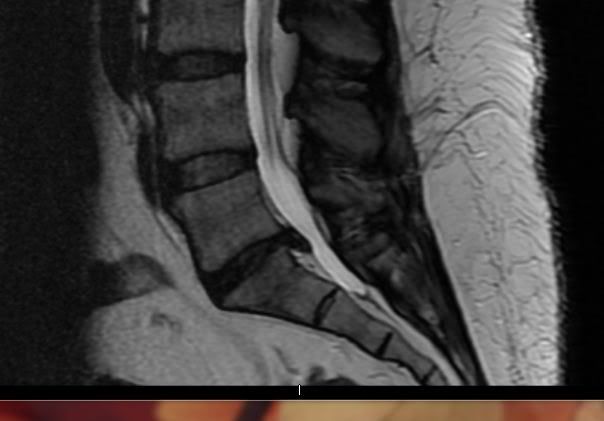

I just had an MRI done and they gave me a disk to take with me for a Doc that will be calling me.

Can anyone tell me how bad is it? Just a heads up on what can be expected.

I won't hold you to your diagnosis.